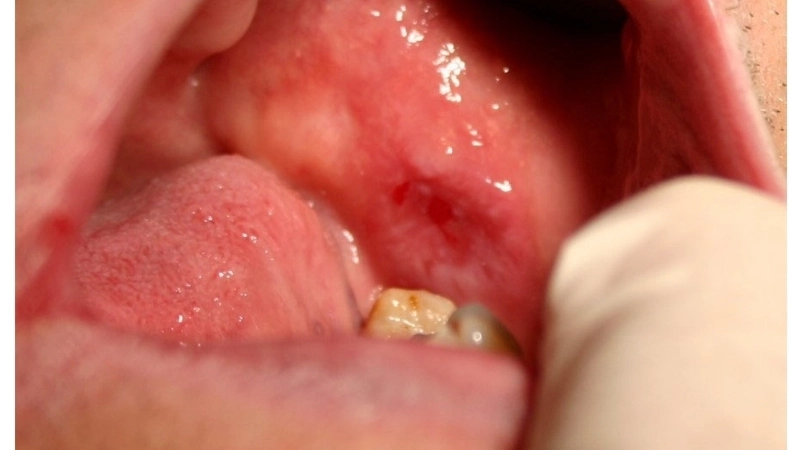

Biểu hiện lichen phẳng ở miệng với các vết loét

• Trên niêm mạc miệng, lichen phẳng ở miệng thường có dạng lưới màu trắng, có thể gây đau rát, đặc biệt khi ăn thức ăn cay nóng.